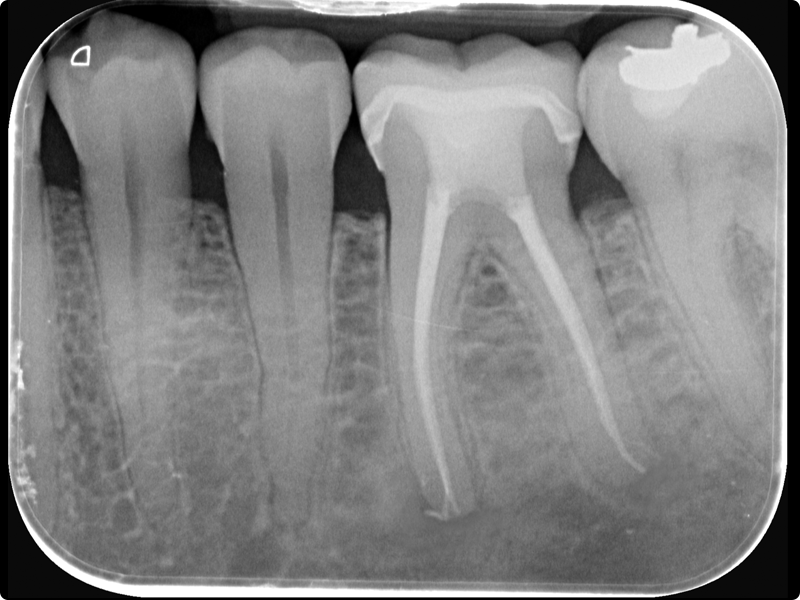

Endodonzia con la sistematica FQ di Komet + Cemento Bioceramico

• Principi e applicazioni della sistematica FQ in situazioni cliniche differenti (canali facili, medi e complessi)

• Le differenti tecniche di otturazione canalare.

• Introduzione al cemento bioceramico: caratteristiche, vantaggi clinici del BioSeal di Komet

• Come integrare il BioSeal nella tecnica di otturazione canalare: protocolli, gestione del cono di guttaperca, detersione, indurimento e prevenzione dell’estrusione

• Sessione pratica su simulatori: utilizzo della sistematica FQ + sperimentazione pratica dell’otturazione canalare con cemento bioceramico